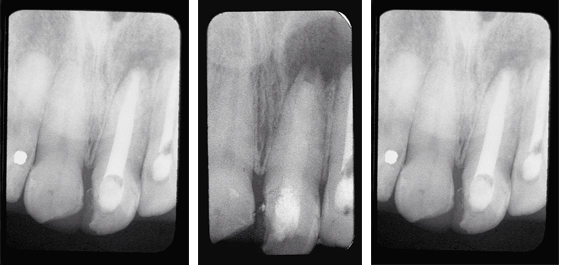

Hard Tissue Formation

This patient lost his maxillary left central incisor due to a traumatic injury.

Fig. 1: Radiograph shows external root resorption on the mesial aspect of the maxillary right central incisor. The root canal was filled with TempCanal to promote healing.

Fig. 2: Radiograph taken 3 months later shows remineralization of the mesial aspect of the tooth.

Treatment of Avulsed Tooth

This child presented with avulsed left central and traumatized right central incisors. Two weeks after replantation and splinting, the pulps were removed and Pulpdent Paste was placed in the root canals. The case was followed regularly for 12 months, and the Pulpdent Paste was changed at each visit. After one year, the root canals were obturated with Pulpdent Root Canal Sealer using the Pressure Syringe technique.

Fig. 1: Photo shows child with avulsed left central and traumatized right central incisor.

Fig. 2: Radiograph taken two weeks following replantation shows replanted tooth, open apices and bone loss. At this visit the root canals were negotiated and Pulpdent Paste was placed as a dressing to stimulate healing and discourage traumatic rejection (not shown).

Fig. 3: Radiograph taken one year after treatment shows Pulpdent Paste in the root canals, apexification and bone fill.